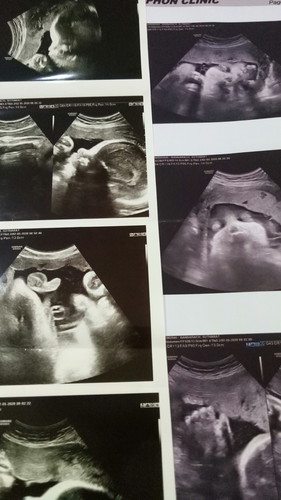

ขอแนะนำตัวเองว่าเรานะ..เราผ่าคลอดไป 1มิ.ย63น้องเป็นผู้ชายน้ำหนัก1900พยาบาลบอกว่าน้องขาดออกซิเจนกับทางพ่อน้องเค้า ส่วนเราเองยังมิเห็นหน้าลูกเลยใจแทบขาด..ไม่รู้มาจากสาเหตุอะไร เพราะก่อนหน้าเราไปหน้าหมอคลีนิคแห่งหนึ่ง ฝากพิเศษเสียด้วย เรารู้สึกเหมือนมีน้ำเหมือกออกมาทางช่องคลอดแต่ไม่เยอะ จึงไปหาหมอหมอตรวจบอกว่า ปากมดลูกไม่เปิดน้ำไม่เดินด้วยจึงให้เรากลับบ้านนัดเราผ่าวันจันทร์เช้าเราไปหาหมอวันเสาร์ช่วงกลางวันกลับมาถึงบ้าน มีเลือดออกมานิดนึงแล้วเราก็นอนพักวันอาทิตย์ไปนอนร.พ อีกแลอาการช่วงตี03.00น.ใกล้รุ่งวันจันทร์รู้สึกอาการไม่ค่อยดีเหงื่อออกมาก แต่หนาวและเย็นมากๆๆพยาบาลมาตรวจฟังหัวใจน้องเต้นอ่อนจึงพาไปฟังคลื่นหัวใจเราถามพยาบาลว่า"น้องเป็นอะไร"พยาบาลว่าน้องอาการไม่ค่อยดี เราดูไม่ออกนะว่าจอโทรทัศน์ที่เขาดูอยู่คือคลื่นหัวใจลูกเรา จึงสั่งหาหมอพิเศษแอดมิดผ่าด่วนเราเริ่มใจไม่ดีแล้ว ผลออกมาน้องขาดออกซิเจน ส่งอบตัวห้องNICU เริ่มแรกเจาะปอด ยาความดันเจาะหัวน้อง ให้เลือดล่าสุดน้องติดเชื้อกระแสเลือด คำพูดที่พยาบาลถามยังคาใจอยู่คือ"ตั้งใจมีลูกคนนี้ไหม"หันมองหน้าแฟนจะตอบพยาบาลไม่ตั้งใจจะพามาฝากพิเศษตั้งแต่ไม่ได้1เดือนไหมแต่เราไม่ตอบ ตอบแค่ว่า"ตั้งใจ"ผ่านไปกลางเดือน17เราต้องเสียลูกได้แต่โทษตัวเอง เรามิน่าชะล่าใจกับทุกอย่างที่เกิดขึ้นมันเร็วมาก ไม่โทษใครแค่อยากเล่าสู่กันฟัง ลูกเราก็มิได้อยู่กับเราแล้วเขาไปสบายแล้ว.... วันหน้าฉันใดหากมีจริงเราขอให้เค้าเกิดมาเป็นลูกเราอีก และให้มาสมบูรณ์ไม่แวะชมห้องไหนแล้ว ออกมาชิมน้ำนมแม่ใช้ชีวิตอยู่กับพ่อแม่พี่น้องนะลูกนะ.....😥😥😥😢😢😭😭😭